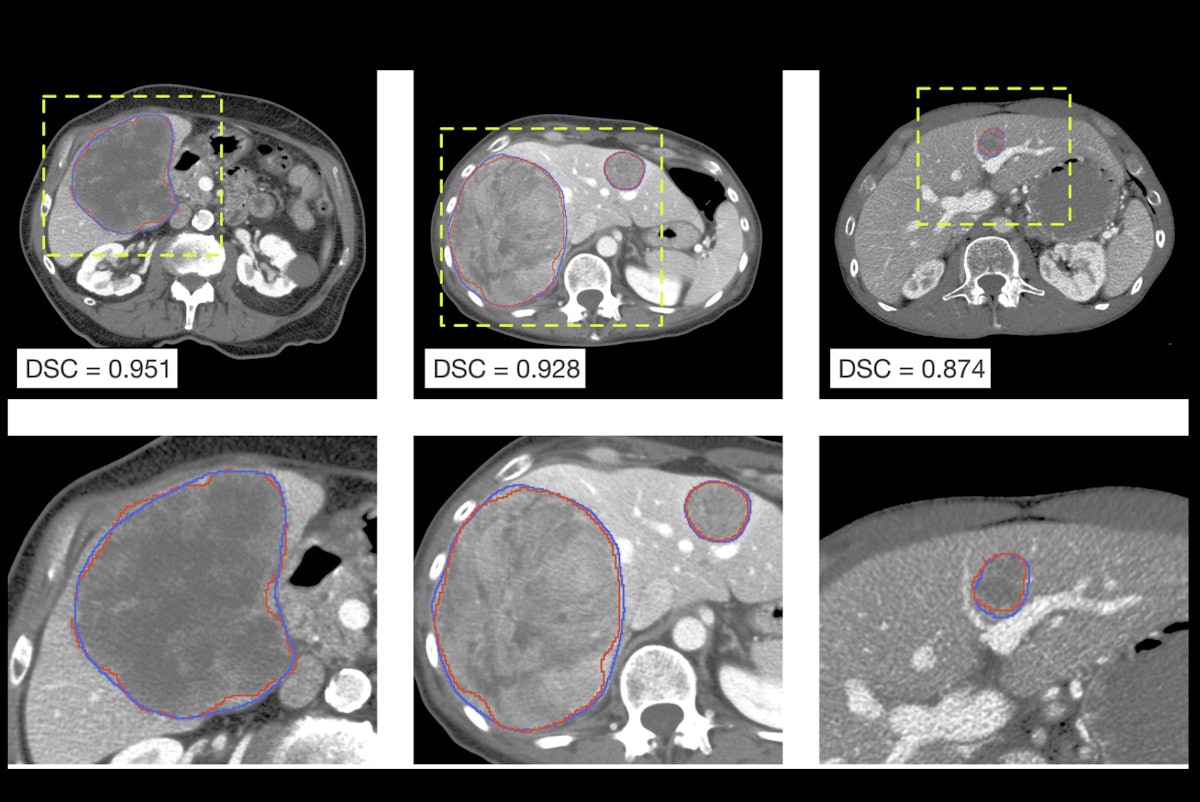

Visual inspection of the automatically delineated contours. Representative cases of liver tumors delineated by SALSA (red) alongside the ground truth (blue) segmented masks. Yellow-dashed boxes indicate the magnification done for better visualization. Image courtesy of Maria Balaguer-Montero, Dr. Raquel Perez-Lopez et al and presented at ECR 2025.

In parallel, the tumor masks automatically generated by SALSA exhibit good overlap with the ground truth. Both approaches reported high values in segmentation metrics for the test and external validation cohorts.

The model showed high accuracy in liver tumor detection with a patient-wise precision of 99.6% and a recall of 94.2% for the external validation cohort. When considering each lesion individually, SALSA obtained a lesion-by-lesion detection precision of 81.7% and a recall of 57.9% in the same dataset, according to the researchers.